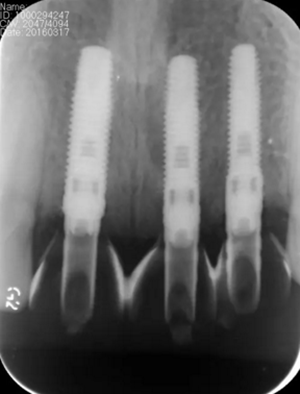

圖13 術(shù)后即刻根尖片

圖17 術(shù)后6個月根尖片

圖24 最終修復(fù)后即刻根尖片

(2)即刻種植、即刻臨時修復(fù)。術(shù)中不翻瓣微創(chuàng)拔除牙根,牙槽 窩骨壁完整。在多級導(dǎo)板輔助下完成種植窩洞制備,植入Bego柱形種植 體,型號分別為:上頜右側(cè)中切牙位點4.1mm×15mm、上頜左側(cè)中切牙 位點?3.75mm×15mm、上頜左側(cè)側(cè)切牙位點3.25mm×15mm,扭矩均為 35N·cm。種植體與唇側(cè)骨壁間隙約2mm,植入Bio-Oss®Collagen骨膠 原。戴入橋用鈦臨時基臺,臨時冠就位順利,自凝樹脂口內(nèi)粘接后適當(dāng)修整 外形,充分磨光,調(diào) 至正中 、前伸 和側(cè)方 與對頜牙均無接觸。術(shù)后 根尖片顯示種植體位置、方向良好。

(5)復(fù)查。種植體周圍骨水平穩(wěn)定,齦乳頭及齦高點位置穩(wěn)定,齦緣 曲線形態(tài)理想,唇側(cè)軟硬輪廓良好,功能滿意,修復(fù)效果符合預(yù)期。